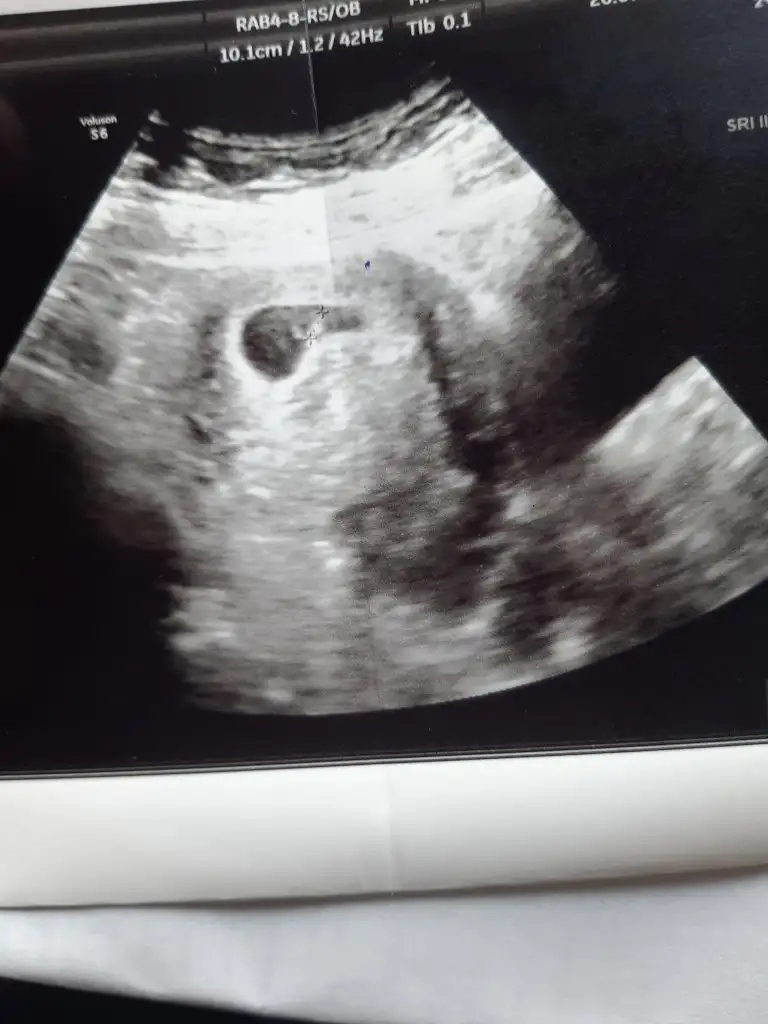

doktordan çıktım daha yeni. Kalp atışını duydum pittik pittik çok şükür

ultrasona göre 6+4 çıktı